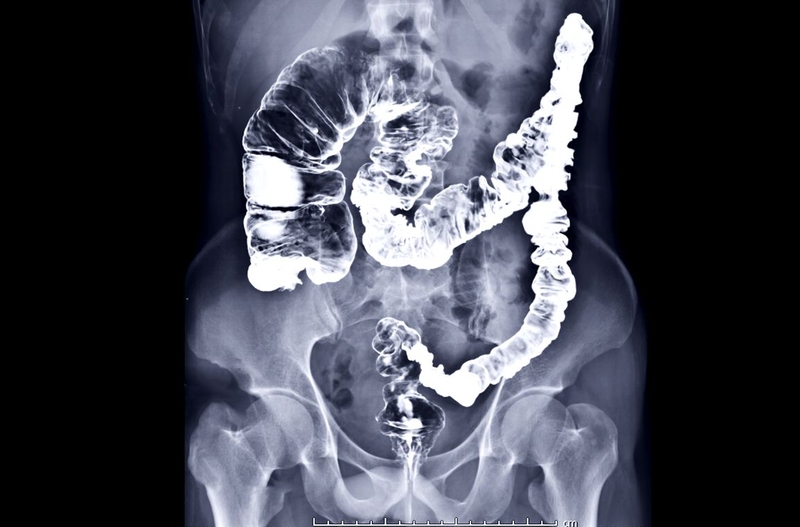

Kỹ thuật chụp X quang đại tràng sử dụng tia X, phát ra từ máy chụp X quang để chiếu xuyên qua đại tràng. Sau đó, hình ảnh đại tràng bên trong cơ thể được ghi lại trên tấm phim hoặc tấm cảm biến. Nhờ đó, các bác sĩ có thể quan sát được hình ảnh cấu trúc bên trong đại tràng. Đây là những hình ảnh sẽ không thể quan sát được bằng mắt thường.

Chụp X quang đại tràng là kỹ thuật chụp X quang có dùng thuốc cản quang. Thuốc cản quang là thuốc có tác dụng tăng hấp thu tia X khi chiếu qua cơ thể. Nó giúp cấu trúc đại tràng được hiện rõ hơn, giúp bác sĩ quan sát và đánh giá đại tràng chính xác hơn. Chất cản quang có chứa một chất kim loại được gọi là Barium. Khi được bơm vào lòng đại tràng, nó sẽ bao phủ lớp niêm mạc trong cùng của lòng đại tràng. Bình thường, tia X phản ánh kém hình ảnh của các mô mềm. Nhưng khi có lớp phủ này, khung đại tràng sẽ hiện lên rõ ràng trên phim chụp.